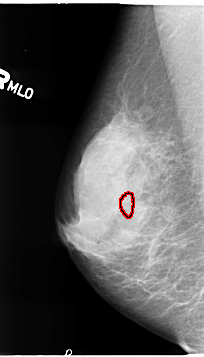

B_3119_1.RIGHT_MLO

RIGHT_MLO LINES 4640 PIXELS_PER_LINE 2648 BITS_PER_PIXEL 12 RESOLUTION 50 OVERLAY

FILE: B_3119_1.RIGHT_MLO.OVERLAY

TOTAL_ABNORMALITIES 1

ABNORMALITY 1

LESION_TYPE CALCIFICATION TYPE PLEOMORPHIC DISTRIBUTION CLUSTERED

ASSESSMENT 4

SUBTLETY 3

PATHOLOGY BENIGN

TOTAL_OUTLINES 1

BOUNDARY